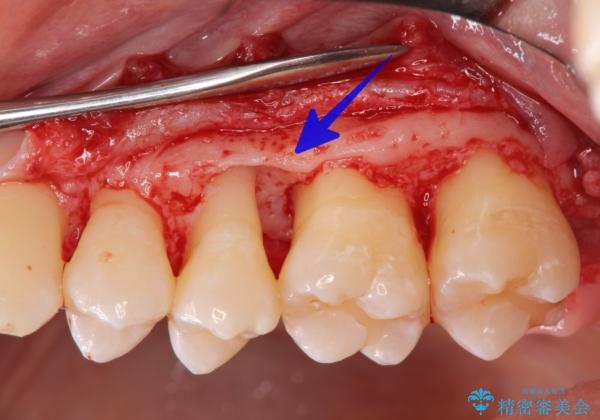

- 他院で歯周病を指摘され、抜歯やインプラント治療が必要と言われたが歯を残す方法はないか?と相談来院されました。

歯周組織検査の結果、歯周ポケットは6mm認められ歯を支えられる歯槽骨が吸収し中等度の歯周病です。

初期治療を行い、歯肉の状態を改善後、骨の形態が良好で再生治療の適応であると判断し、吸収した骨の再生を図る再生治療を行います。

再生治療後は、歯の揺れを抑えるためにワイヤー固定を行い、約1年後に歯周ポケットの値を再計測したところ6mm → 3mmと大幅な改善が認められました。